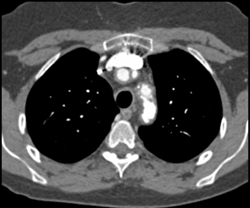

Diagnosis

Type B Dissection